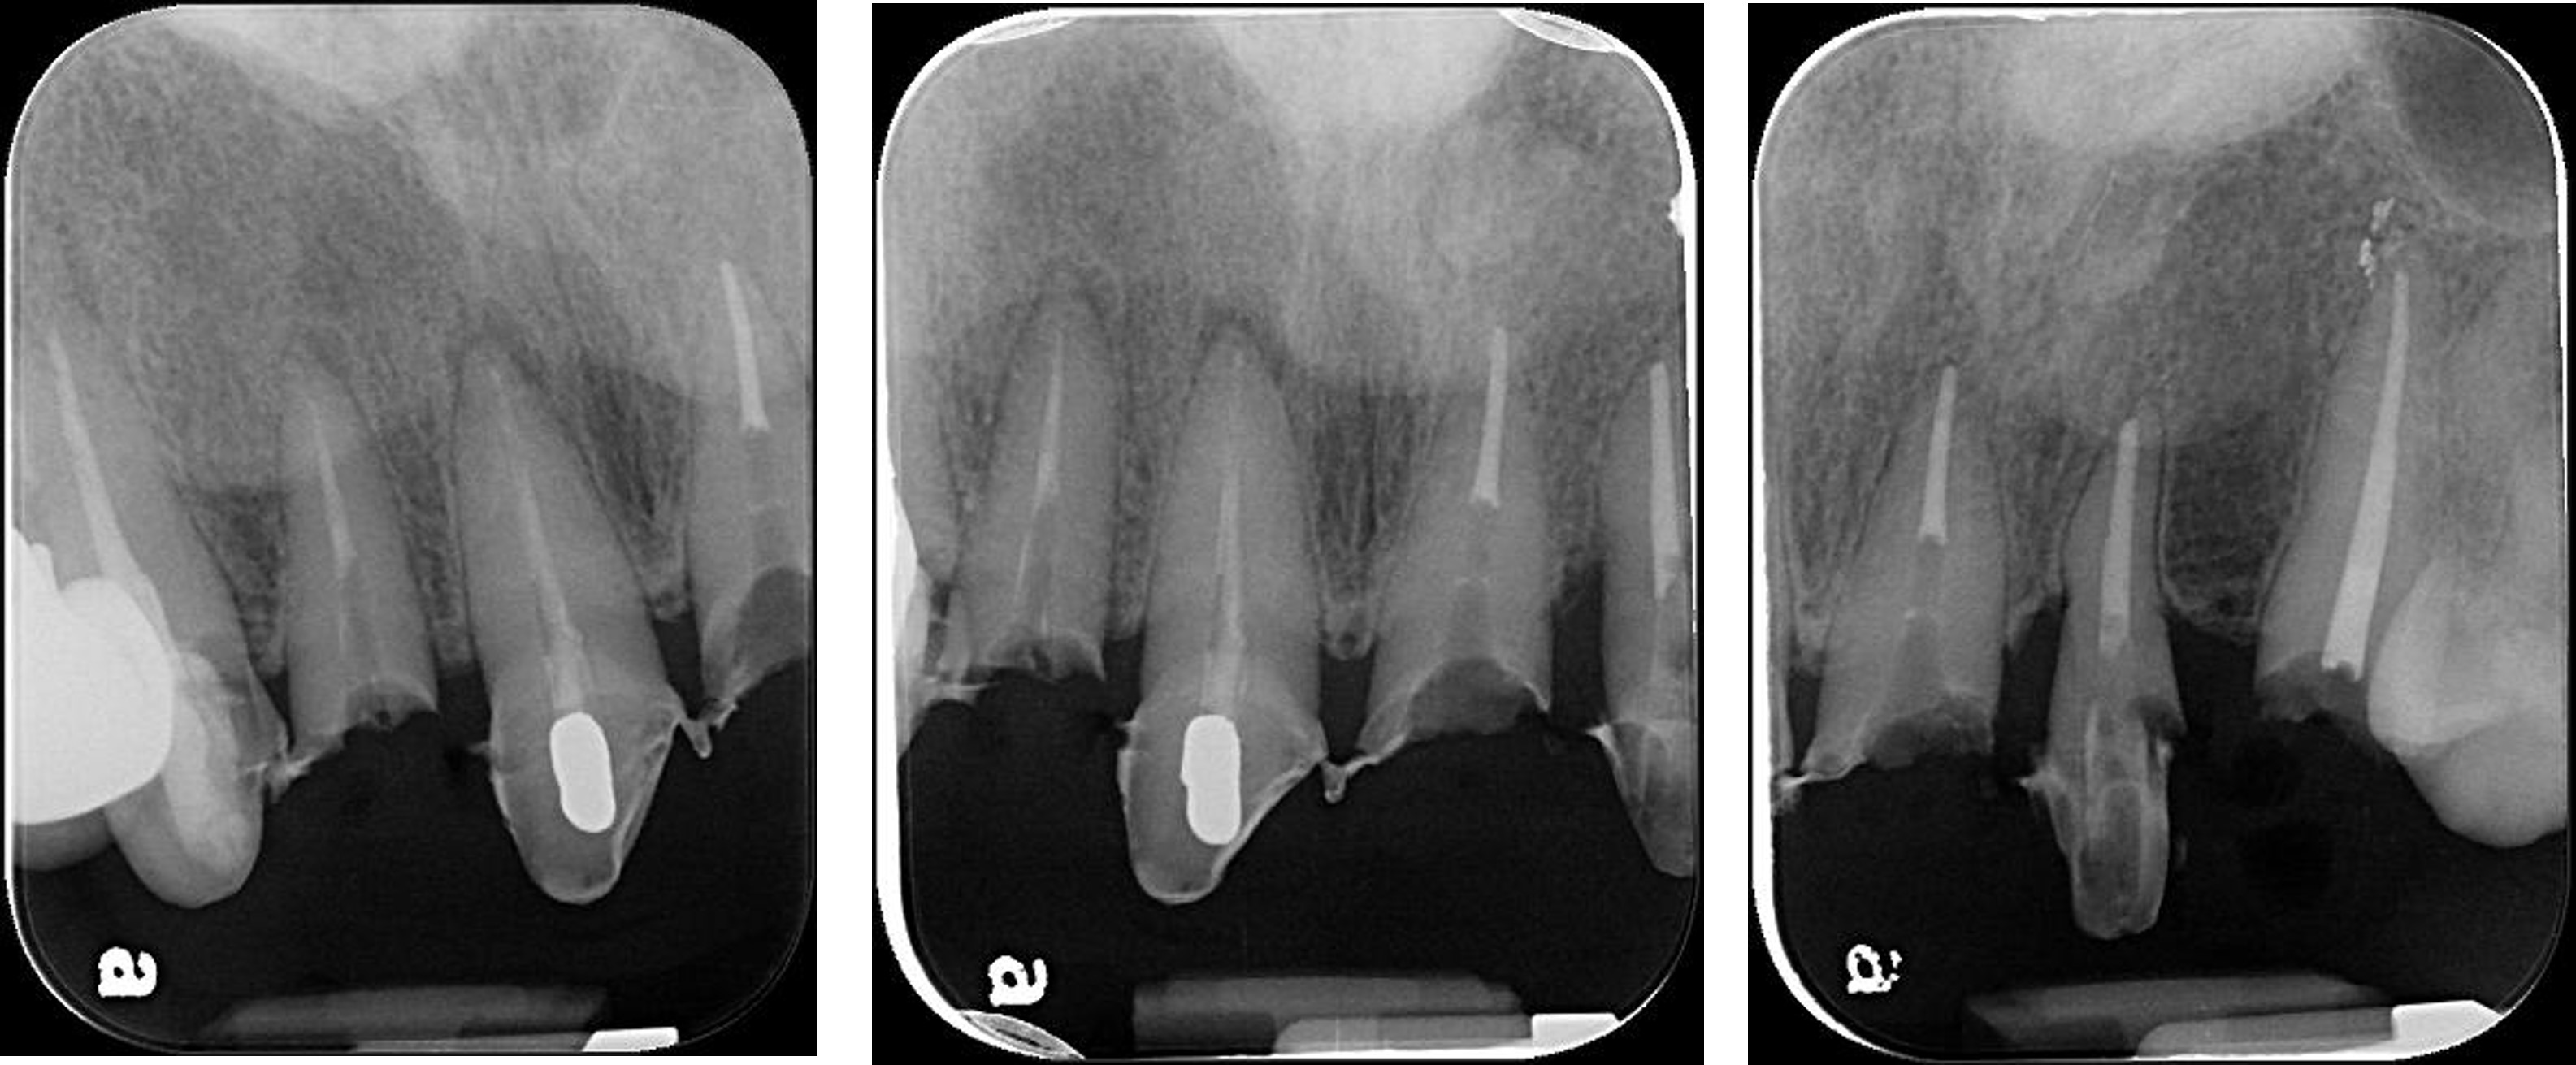

顯微根管治療:#12

顯微根管治療:#11

前牙金屬釘柱復形